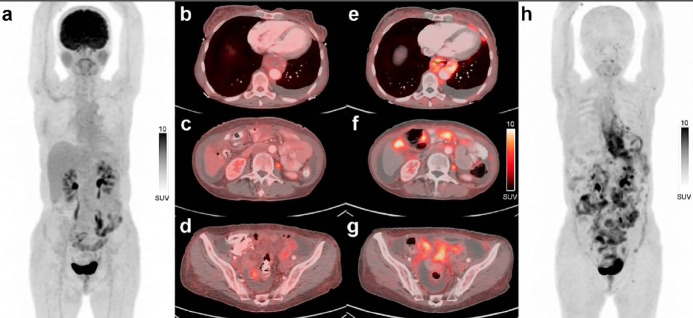

Results: 68Ga-FAPi PET/CT imaging was performed in 30 patients with 18F-FDG-negative or indeterminate lesions. Of the 30 patients, 23 had gastric cancer and 7 had colorectal cancer. Among all patients, histopathological diagnosis of signet ring cell carcinoma was present in 15 (50%) patients. Primary tumor or local recurrence was detected in 19 (63%) patients, lymph node metastasis in 8 (27%) patients, visceral metastasis in 4 (13%) patients, peritoneal metastasis in 14 (47%) patients, and bone metastasis in 3 (10%) patients on 68Ga-FAPi PET/CT images. All patients underwent histopathological confirmation on 68Ga-FAPi PET/CT images. The disease stage was upgraded in 20 patients (67%) after 68Ga-FAPi PET/CT imaging. Of the 20 patients, 12 had no evidence of recurrence or metastasis on 18F-FDG PET/CT.

Conclusion: Based on our study, 68Ga-FAPi PET/CT alters the disease stage in the majority of gastrointestinal malignancies with negative or equivocal 18F-FDG PET/CT findings. 68Ga-FAPi PET/CT appears to be effective in both staging and restaging of gastrointestinal malignancies, such as signet-ring cell carcinomas of the stomach that frequently show low 18F-FDG -avidity.